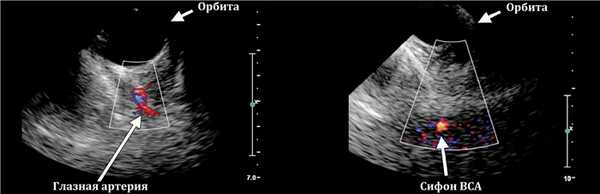

Для височного и орбитального доступа пациент в положении лежа на спине; доступ через большое затылочное отверстие со стороны затылка.

Орбитальный доступ через верхнее веко при закрытых глазах пациента; можно видеть глазную артерию и поперечный срез сифона ВСА.

Доступ через висок кпереди, над и кзади от ушной раковиной: можно видеть СМА, ПМА, ЗМА, ПСА, ЗСА, поперечный срез, СМВ, вены Розенталя и Галена, прямой синус.